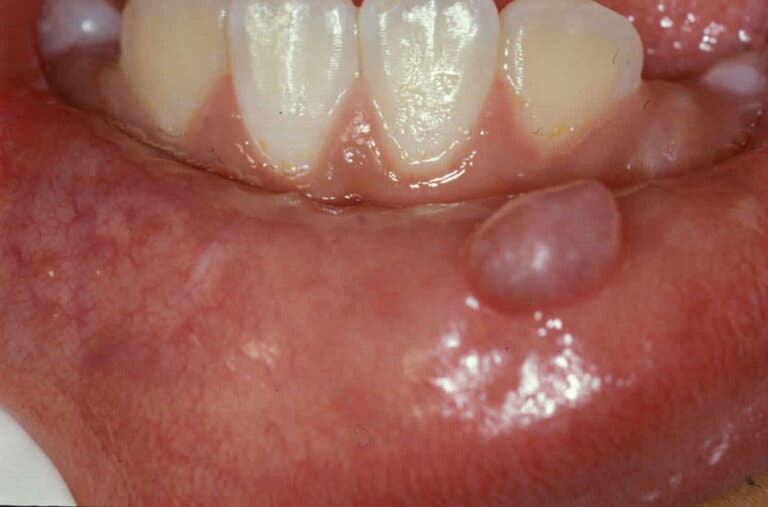

El mucocele se manifiesta de forma súbita como una pequeña ampolla o nódulo lleno de moco en el interior de la boca, en general en el labio inferior. Puede ser de coloración azul translúcida o mantener el mismo tono de la mucosa subyacente. Son indoloros, a menos que se acompañen de una herida.